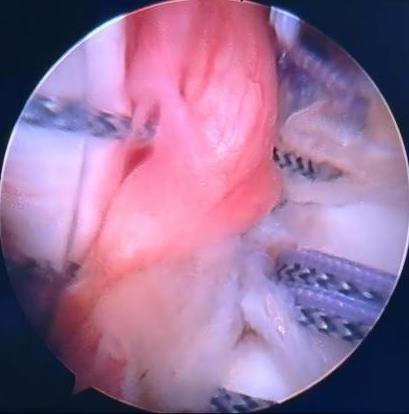

摘要:目的 探讨常规切开Latarjet手术、关节镜下Latarjet手术、关节镜下Bankart修复联合Remplissage手术在肩关节复发性前脱位(RASD)合并肩胛骨关节盂骨缺损 > 15%及啮合性Hill-Sachs损伤中的应用效果及安全性。方法 回顾性分析该院2022年1月-2024年12月收治的65例RASD合并肩胛骨关节盂骨缺损15%~25%及啮合性Hill-Sachs损伤患者的临床资料,根据手术方法的不同,分成A、B和C组;其中,A组实施常规切开Latarjet手术(n = 18),B组实施关节镜下Latarjet手术(n = 21),C组实施关节镜下Bankart修复联合Remplissage手术(n = 26)。比较3组患者手术情况、手术前后相关量表评分[视觉模拟评分法(VAS)、Constant-Murley肩关节评分和加州大学洛杉矶分校(UCLA)肩关节评分等]和肩关节活动度,以及术后并发症和复发情况。结果 手术时间:B组长于A组和C组(P < 0.05),A组长于C组(P < 0.05)。术中出血量和住院时间:A组多于或长于B组和C组(P < 0.05),B组多于或长于C组(P < 0.05)。3组疼痛VAS评分:术后1、6和12个月都低于同组术前(P < 0.05)。术后1和6个月疼痛VAS评分:A组均高于B组和C组同期(P < 0.05)。术后1个月疼痛VAS评分:B组高于C组(P < 0.05)。术后12个月疼痛VAS评分:3组差异不明显(P > 0.05)。比之同组术前,A组术后6和12个月,B组和C组术后1、6和12个月,UCLA肩关节评分均明显升高(P < 0.05)。术后1个月UCLA肩关节评分:A组低于B组和C组(P < 0.05),B组低于C组(P < 0.05)。术后6和12个月UCLA肩关节评分:3组患者差异均不明显(P > 0.05)。比之同组术前,A组术后6和12个月,B组和C组术后1、6和12个月Constant-Murley评分均明显升高(P < 0.05)。术后1个月Constant-Murley肩关节评分:A组低于B组和C组(P < 0.05)。术后6和12个月Constant-Murley肩关节评分:3组患者无明显差异(P > 0.05)。3组患者前屈上举活动度:术后12个月都大于同组术前(P < 0.05)。术后12个月前屈上举活动度:3组患者无明显差异(P > 0.05)。术前、术后12个月体侧外旋、外展90°外旋活动度:A组和B组组内和同期组间均无明显差异(P > 0.05)。C组体侧外旋、外展90°外旋活动度:术后12个月小于术前(P < 0.05)。术后12个月体侧外旋、外展90°外旋活动度:A组和B组均大于C组(P < 0.05)。术后并发症发生率和复发率:3组患者无明显差异(P > 0.05)。结论 常规切开Latarjet手术、关节镜下Latarjet手术、关节镜下Bankart修复联合Remplissage手术治疗RASD合并肩胛骨关节盂骨缺损15%~25%及啮合性Hill-Sachs损伤,均能有效改善肩关节功能及缓解疼痛,但两种肩关节镜手术的创伤更小,术后恢复更快。